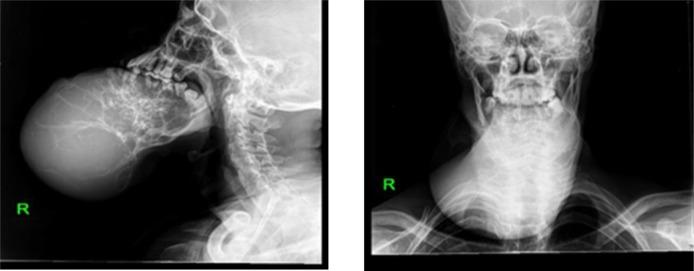

The presented case was of a 30 years old man from South Ethiopia, with a giant keratocystic odontogenic tumor of the mandible.

该病例为一名来自埃塞俄比亚南部的30岁男性,患有下颌骨巨大牙源性角化囊性瘤。